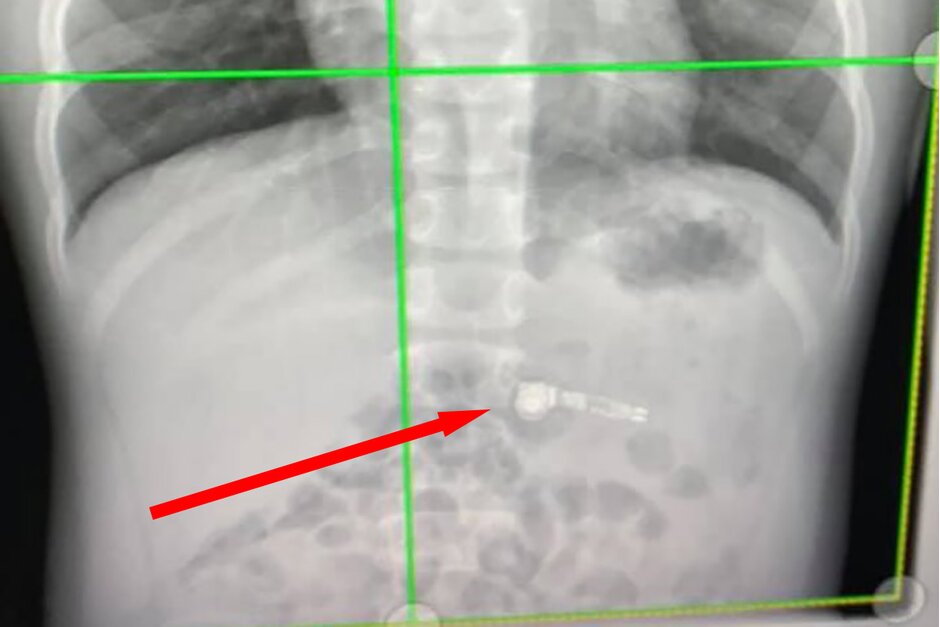

Tại trung tâm nhi khoa Atlanta Egelston, các bác sĩ cũng tỏ ra rất bối rối vì vấn đề mình gặp phải xong hình ảnh chụp X-quang đã phát hiện ra những linh kiện kim loại trong chiếc AirPods và xác nhận rằng đứa trẻ đã nuốt chiếc tai nghe này.